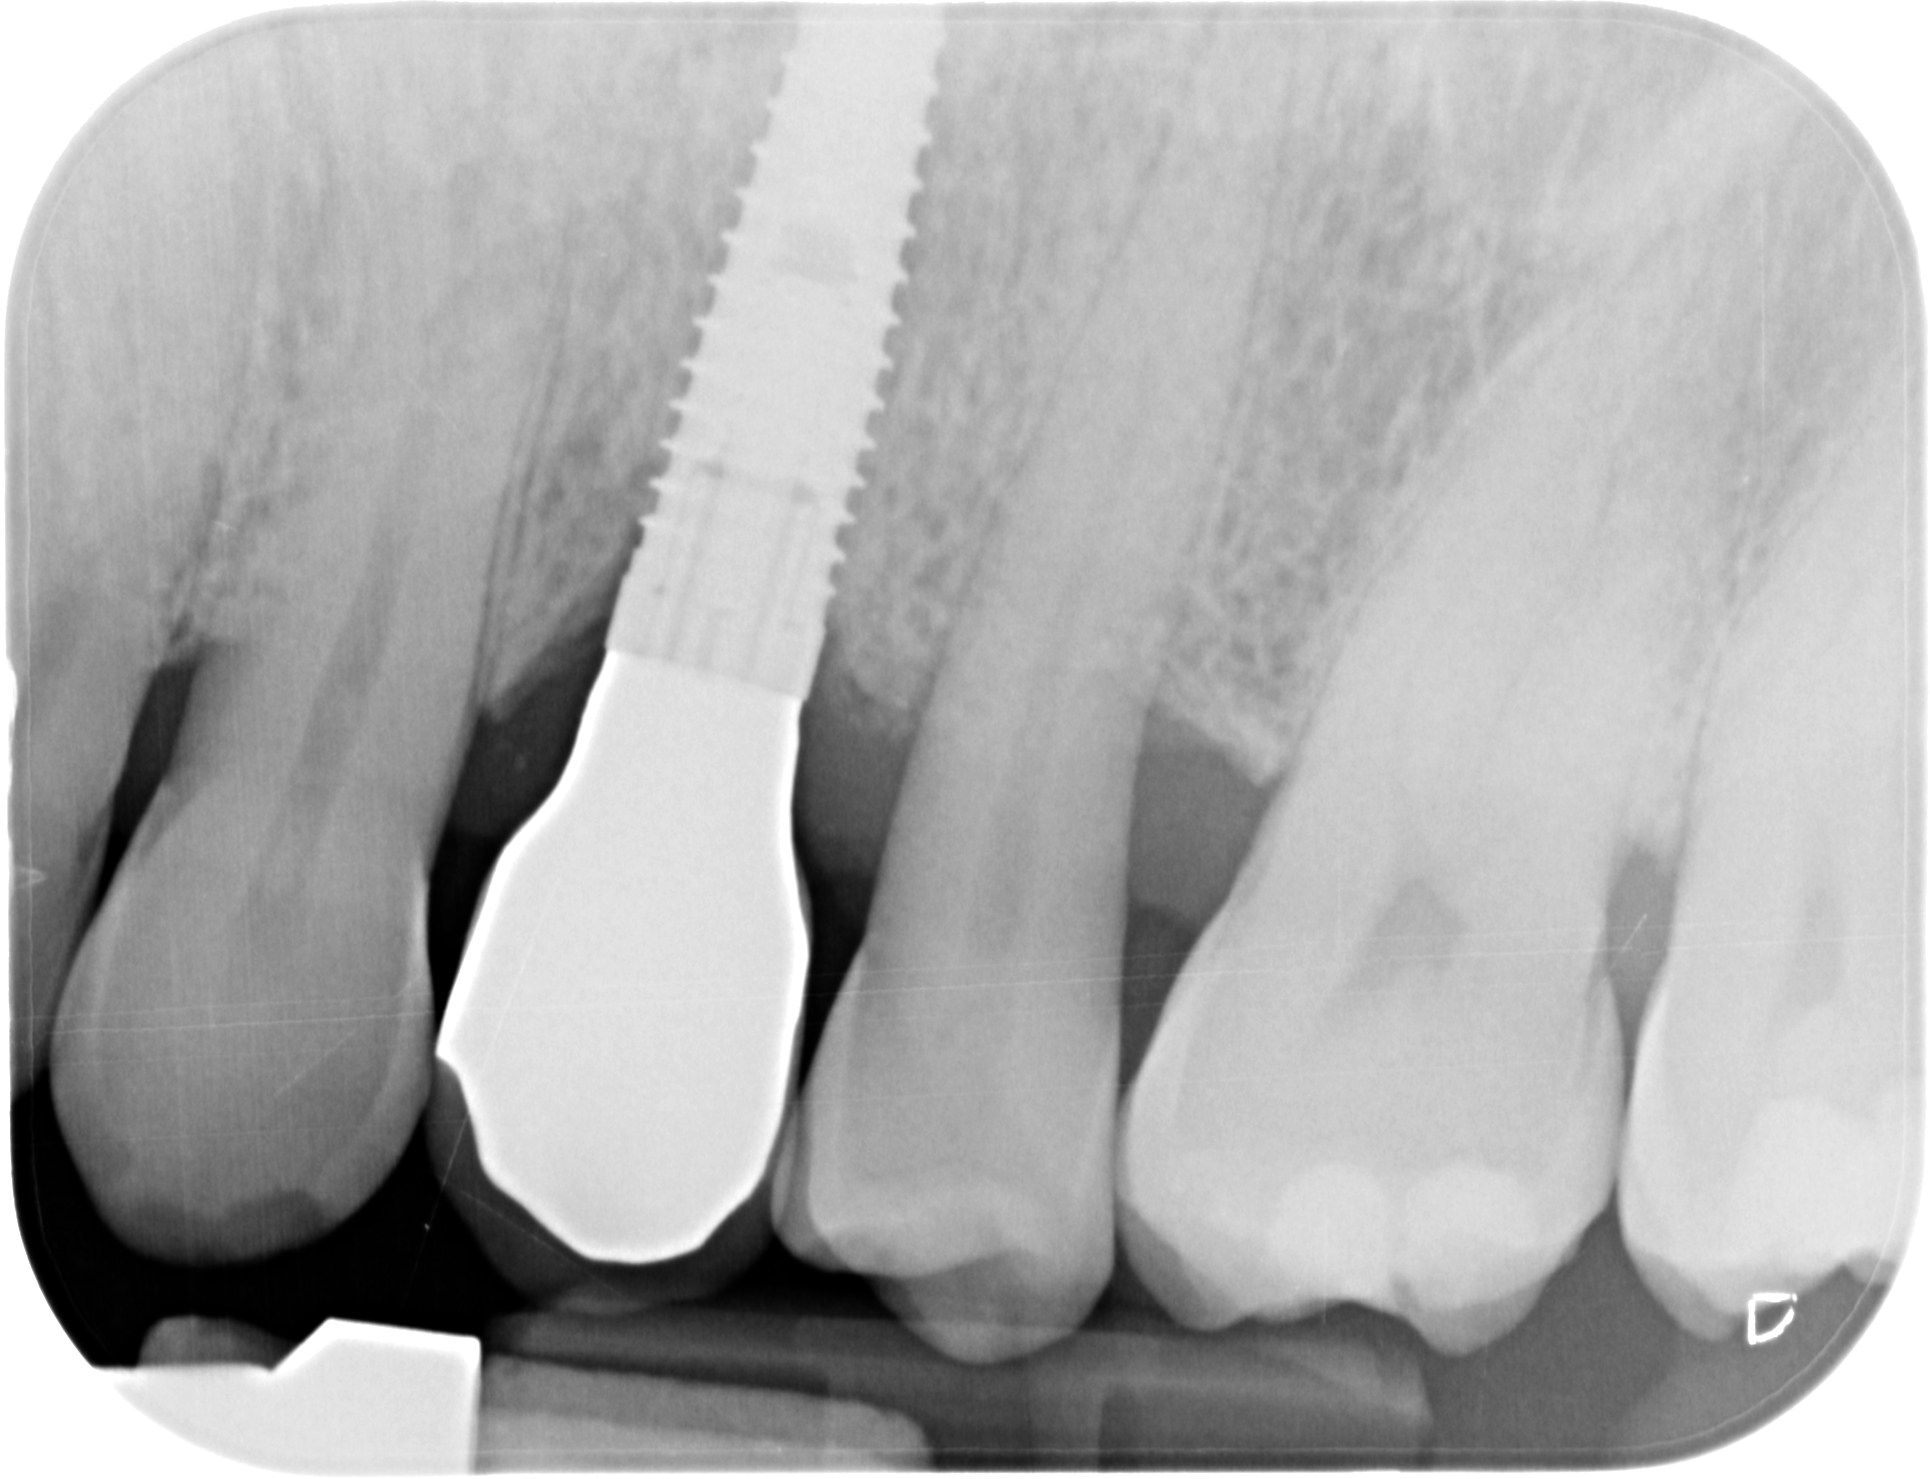

Implantes e implantoprótesis en Segovia

Es la especialidad dedicada a reponer los dientes perdidos/ausentes mediante la colocación de un implante, un “tornillo” de titanio anclado al hueso, y que una vez se ha osteointegrado (soldado al hueso), permite colocar una corona protésica atornillada directamente al implante.

En Clidentse contamos con el Dr. Ángel Silmi para esta especialidad, que es sin duda la opción ideal y más conservadora para reponer los dientes perdidos y/o ausentes. De otra forma, la prótesis fija convencional sobre

diente exige tallar (desgastar) los dientes adyacentes a la ausencia, los cuales hacen de pilares de un puente de 3 piezas para reponer el diente perdido. Con los implantes dentales, esta antigua opción terapéutica fija está desaconsejada. Hoy día se tiende a hacer una Odontología Mínimamente Invasiva. Y tallar los dientes supone un tratamiento excesivamente traumático y debilitante. La resistencia de los dientes está relacionada directamente con la cantidad de diente sano remanente.